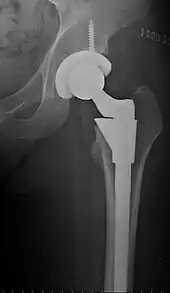

![]() An X-ray showing a left hip (right of image) that has been replaced, with the ball of this ball-and-socket joint replaced by a metal head that is set in the femur and the socket replaced by a cup | |